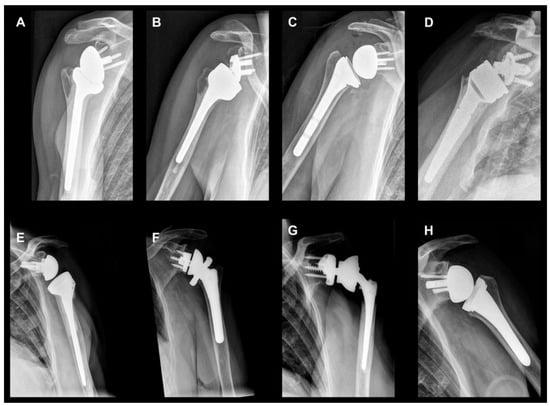

2. Biomechanical Considerations

3.3. Humeral Component

3.4. Polyethylene Humeral Inlay